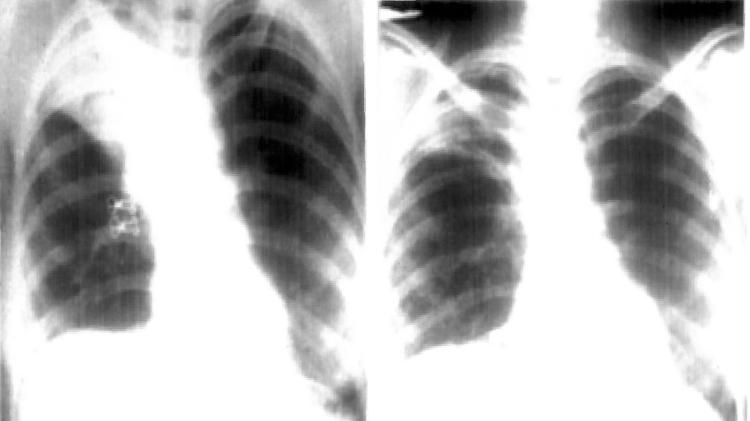

Raio-x de pulmão após inalação acidental de camisinha - Reprodução/C. L. Arya, R. Gupta, V. Arora/Semantic Scholar  - Reprodução/C. L. Arya, R. Gupta, V. Arora/Semantic Scholar

Raio-x de pulmão após inalação acidental de camisinha

Porém, o teste deu negativo para a doença: havia, na verdade, uma lesão em um lobo pulmonar superior da paciente, resultado da inalação do preservativo.

Os profissionais de saúde só perceberam isso ao examinarem o tórax dela e notarem uma “estrutura semelhante a uma bolsa invertida ‘parada’ no brônquio”. Quando os médicos removeram cirurgicamente essa “bolsa”, eles entenderam finalmente que se tratava da camisinha.